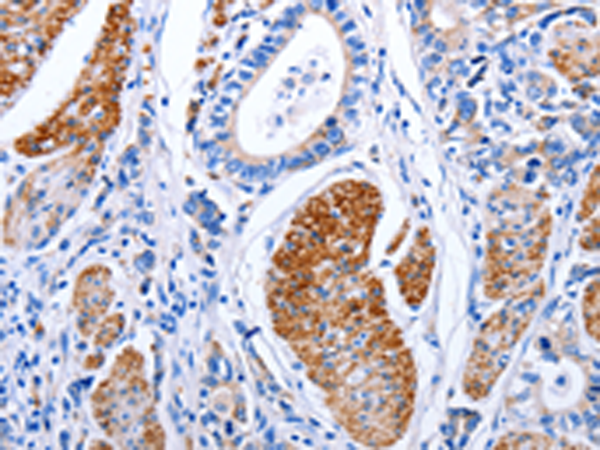

分类: 科研抗体货号: P11014别名: sMAP; MAP19; MASP-2; MASP1P1应用: IHC反应种属: Human, Mouse, Rat